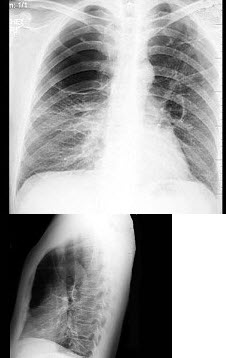

7、单项选择题

男,48岁,常感胸闷气逼,近1月渐加重,X线检查如图,最可能的诊断是()

A.右侧气胸

B.右侧肺大泡

C.两肺肺大泡

D.正常胸片

E.肺气肿